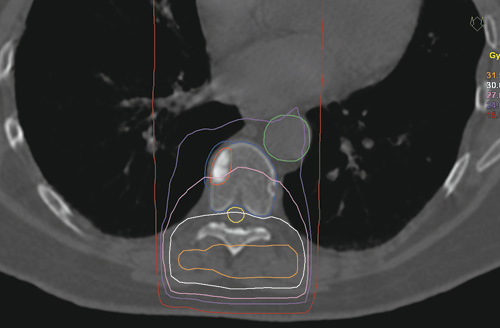

Konvensjonell strålebehandling med et enkelt feltoppsett innebærer en lite ressurskrevende planleggingsprosess og er et veletablert behandlingstilbud for disse pasientene. Man gir vanligvis ti daglige behandlinger à 3 gray (Gy), eller sjeldnere en engangsbehandling med 8 Gy, og hele stråledosen gis inn rett bakfra. Siden medulla spinalis dermed uvegerlig blir liggende inne i det bestrålte området, må behandlingsdosen legges under den optimale terapeutiske dosen for å unngå overdosering til medulla (fig 1). Ryggmargen er et strålefølsomt organ, og for høye doser til denne kan i verste fall føre til lammelser. Muligheten for varig lokal tumorkontroll er derfor relativt liten (4)-(6). Dersom en tidligere bestrålt ryggradsmetastase øker i størrelse eller det oppstår metastaser i nabovirvler, kan konvensjonelle fraksjoneringer og behandlingsopplegg også være problematiske, siden effekten av tidligere strålebelastning på medulla i liten grad er reparert.

Den beregnede dosefordelingen gir betydelig høyere svulstdose, og en tilfredsstillende skjerming av risikoorganene i nærheten av behandlingsområdet, sett i forhold til konvensjonell behandling. Tumorområdet får over 18 Gy (midlere strålingsdose 24 Gy), mens medulla får maksimalt 12 Gy. Til sammenlikning er dosefordelingen fra et tradisjonelt opplegg, der 30 Gy gis i ti fraksjoner, vist i figur 1.